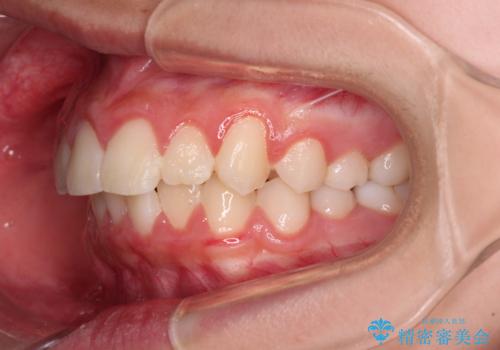

気がつくと唇があいてしまう ワイヤー装置での抜歯矯正

- 口元の突出感で口が閉じにくいとのことで来院された患者様です。

上下左右の第一小臼歯4本を抜歯し、ワイヤー装置での抜歯矯正を行うこととしました。

口元の突出感が解消され、睡眠時の口呼吸が改善されました。